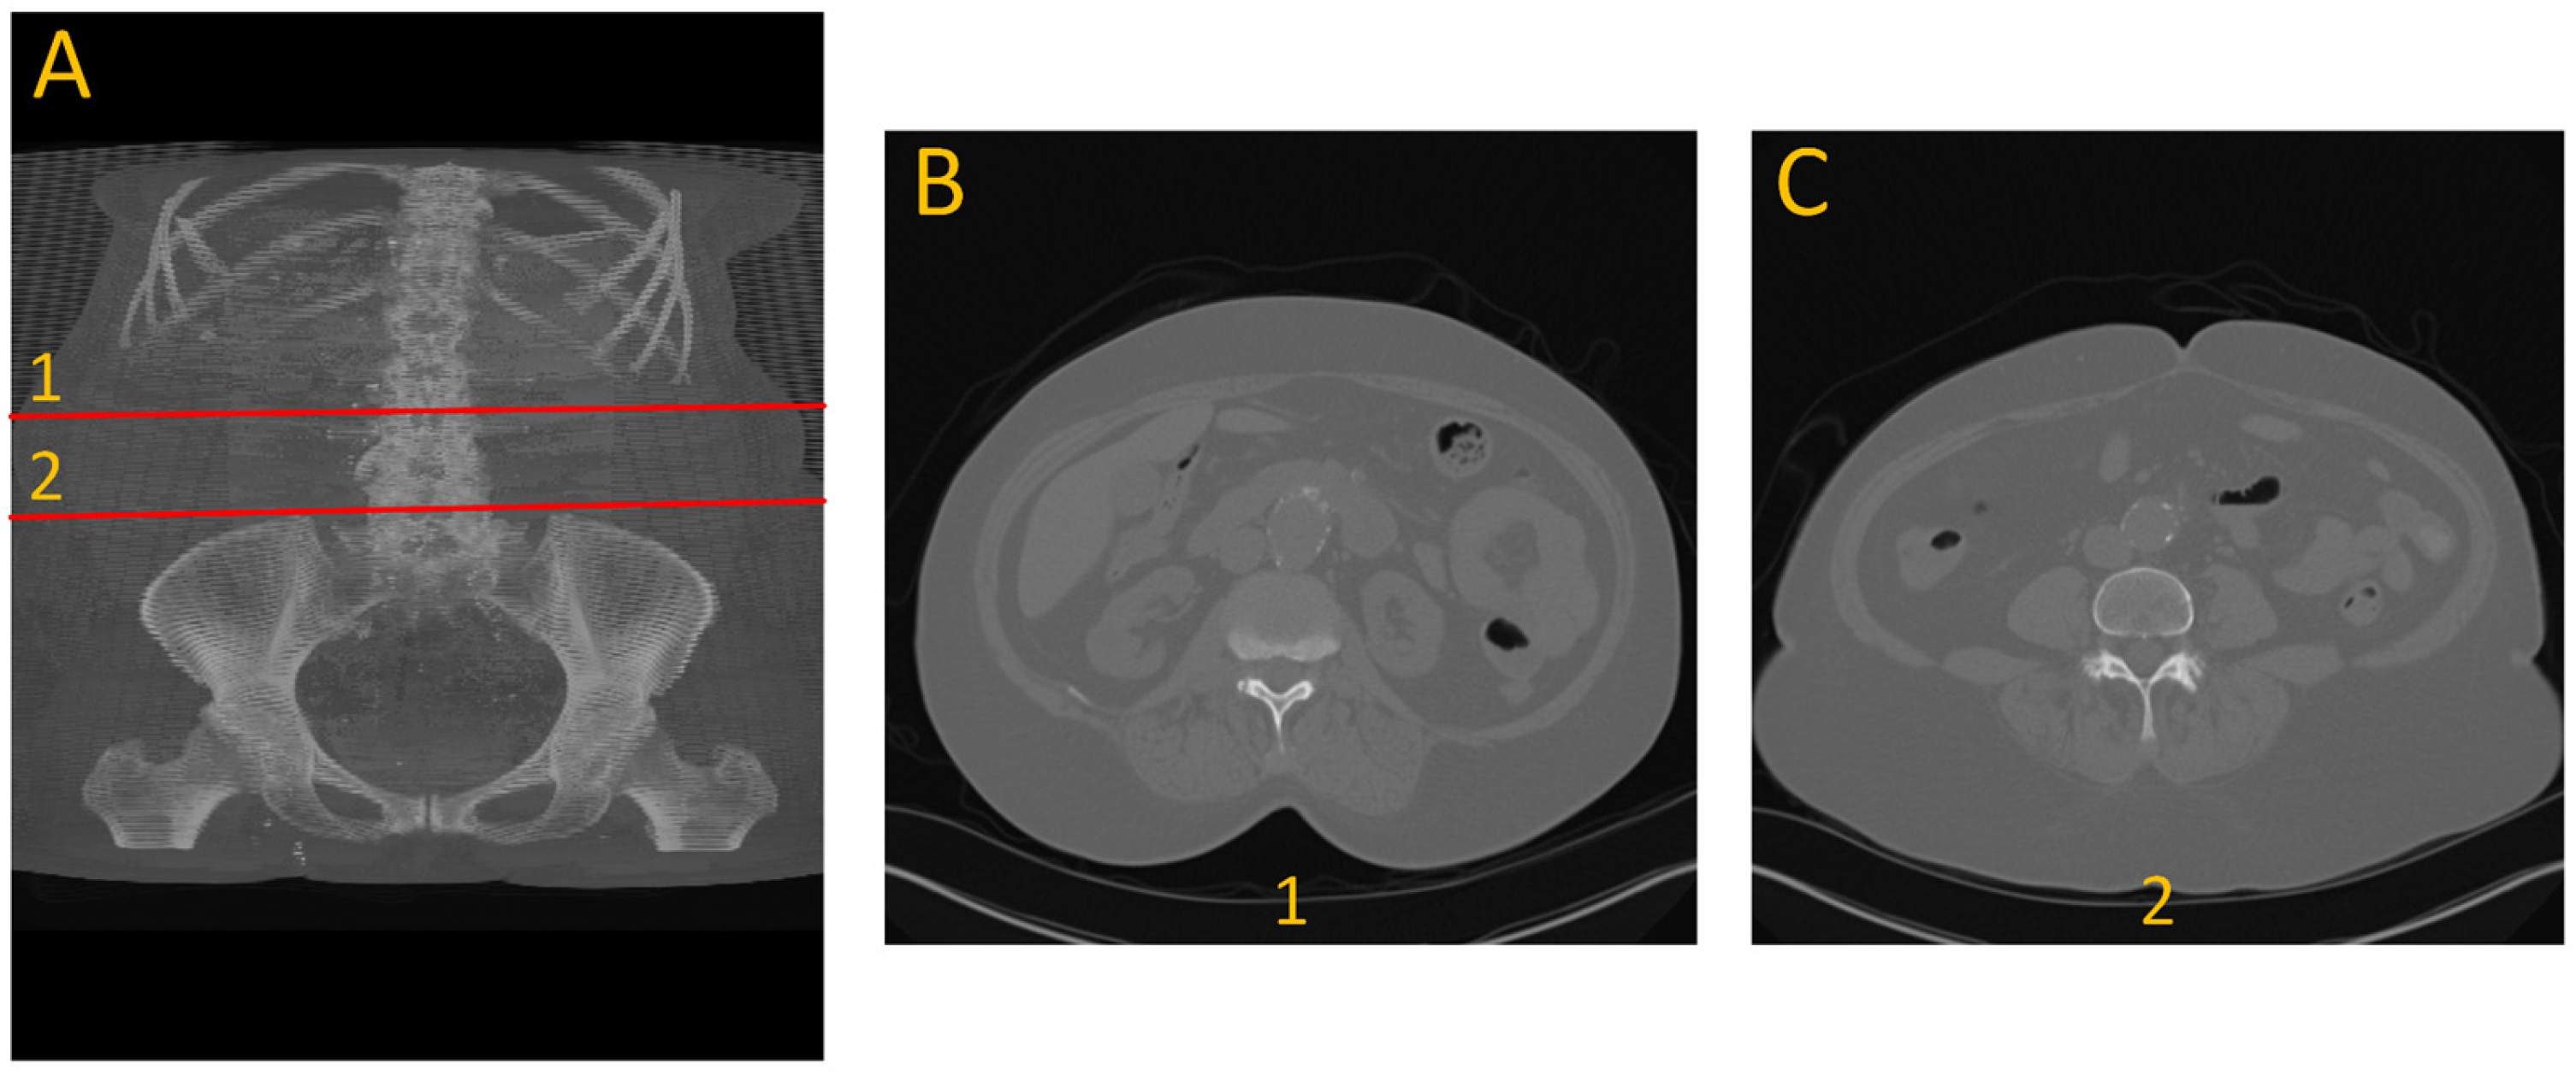

To generate ground truth for aneurysm boundaries, patient scans were manually annotated by an expert in arterial mechanics. The manual annotation process involved identifying the specific slice indices corresponding to the onset and conclusion of the aneurysm, based on morphological changes, primarily variations in cross-sectional diameter, as shown with number 1 and 2 in Figure 1.

Figure 1. Example of the dataset. (A) 3D view front with annotation of the beginning (1) and end (2) of aneurysm. (B) cross-section view of the beginning of the aneurysm. (C) cross-section view of the end of aneurysm.